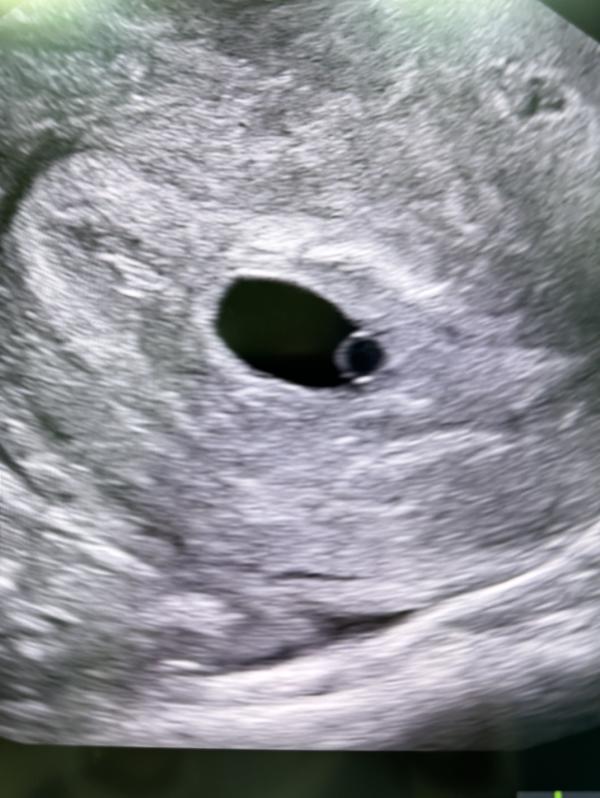

Развитие плода на 6 и 16 неделях беременности

6 недель и 16 недель, с такой маленькой капельки целый человечек, Аллагьума Барик